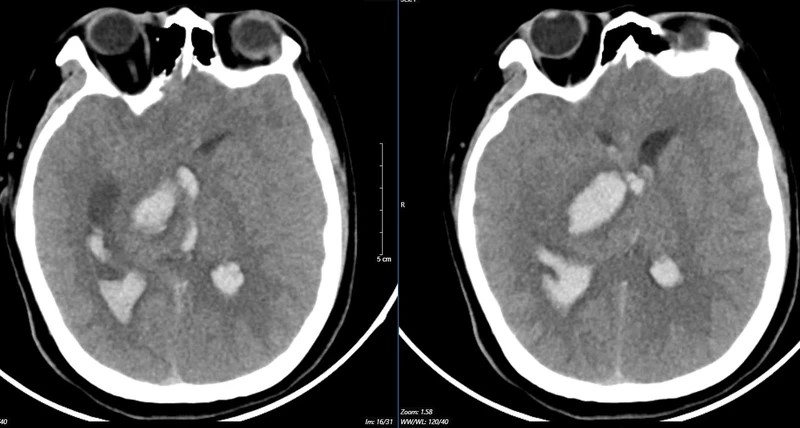

Kết quả chụp lại phim MSCT mạch não chảy máu não đồi thị - não thất do vỡ khối AVM của bệnh nhân 15 tuổi. |

Bệnh nhân 15 tuổi đến viện vì đột ngột đau đầu dữ dội. Bệnh nhi nhanh chóng rơi vào tình trạng hôn mê. Bệnh viện tuyến dưới tiếp nhận chẩn đoán bệnh nhi bị chảy máu não, lập tức được đặt ống nội khí quản thở máy và nhanh chóng chuyển ngay đến Bệnh viện Bạch Mai.

Bệnh nhân vào Trung tâm Đột quỵ, Bệnh viện Bạch Mai trong tình trạng hôn mê sâu, Glasgow 5 điểm, thở máy, giãn đồng tử bên phải. Kết quả chụp lại phim MSCT mạch não chảy máu não đồi thị - não thất do vỡ khối AVM (dị dạng thông động- tĩnh mạch não) biến chứng giãn não thất cấp, rối loạn thân nhiệt, sốt cao liên tục 39-40 độ C.

Theo các bác sĩ, khối dị dạng mạch não tuy không quá lớn nhưng ở vị trí cực kỳ nguy hiểm. Mặc dù đã được hồi sức tích cực tại Trung tâm Đột quỵ nhưng tình trạng diễn biến nhanh, bệnh nhân tụt huyết áp, thiểu niệu, rối loạn thân nhiệt, hôn mê sâu Glasgow 3 điểm.